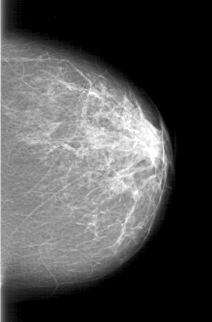

D_4197_1.LEFT_MLO

LEFT_MLO LINES 5116 PIXELS_PER_LINE 3841 BITS_PER_PIXEL 12 RESOLUTION 43.5 NON_OVERLAY